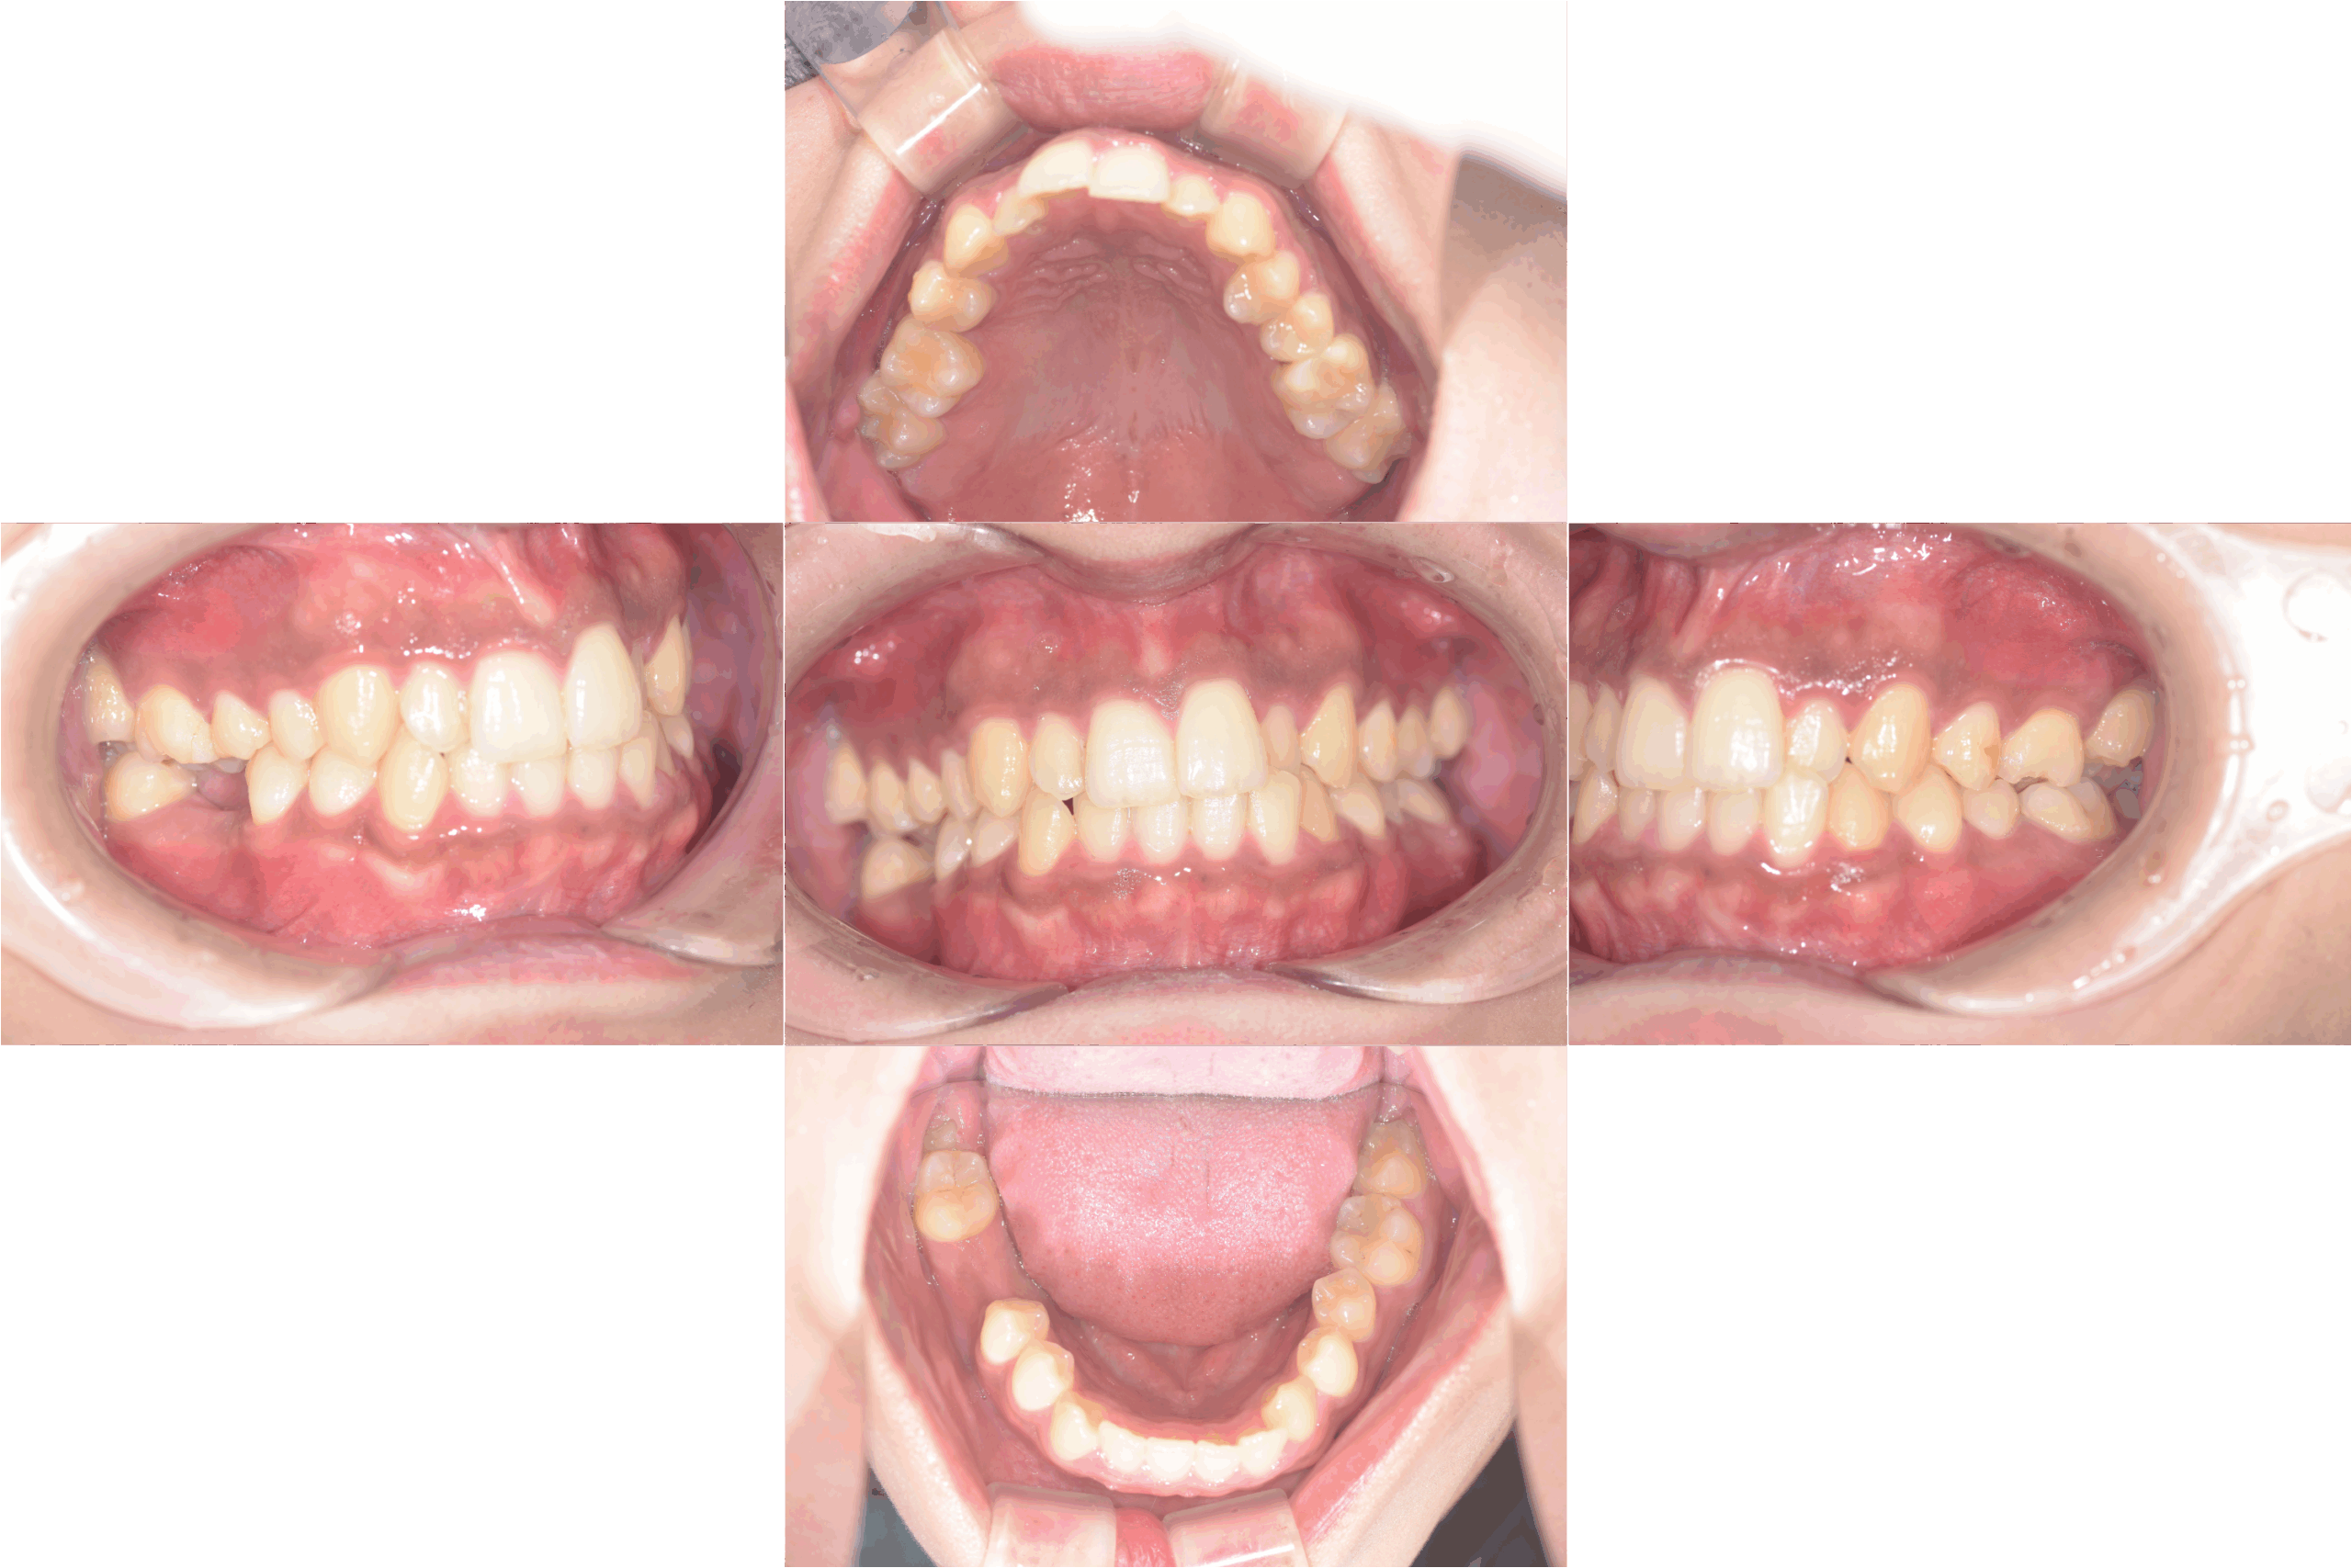

治療前口腔内写真

治療後口腔内写真